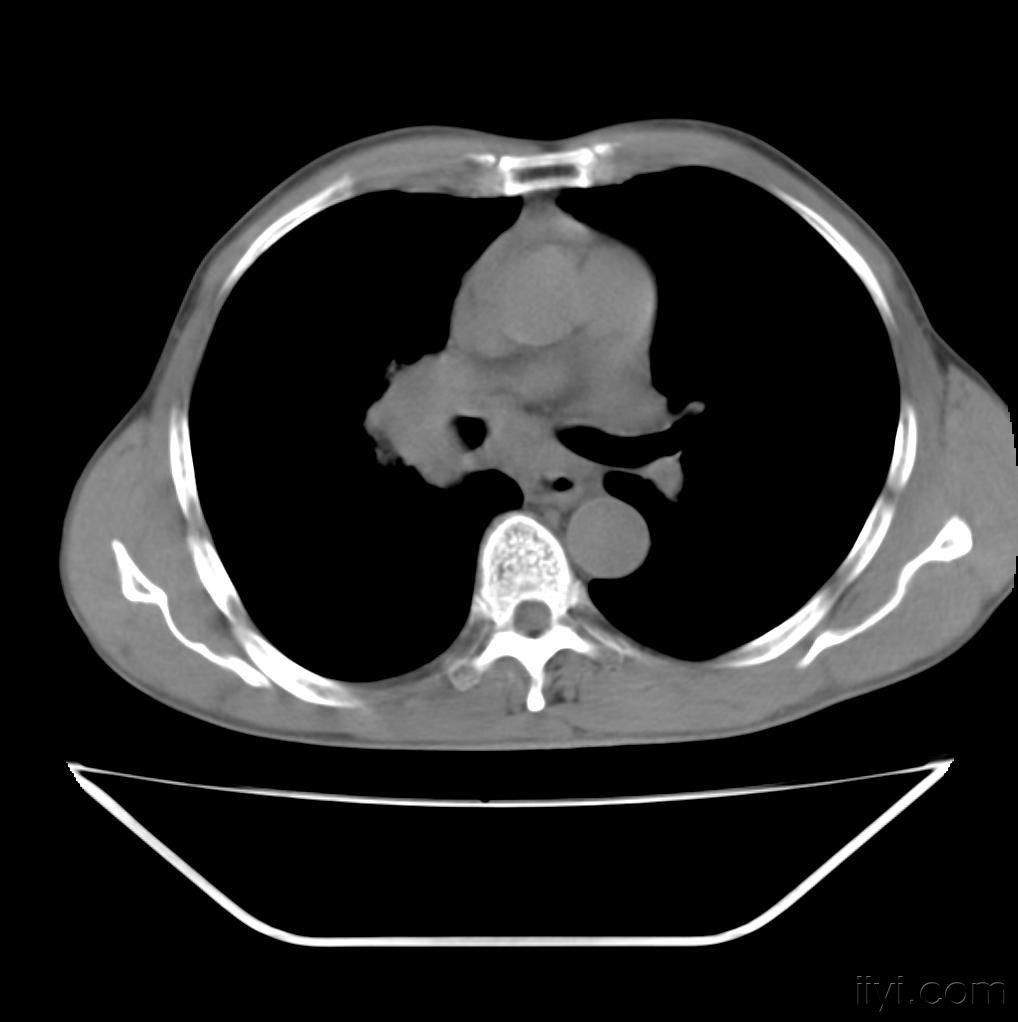

患者81岁,男性,查体发现左肺肿瘤. 2009.2.12入院时胸部ct扫描

图片尺寸1600x750